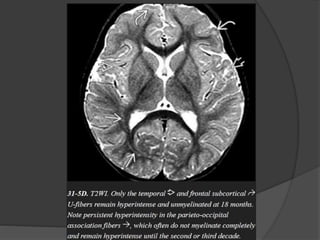

 Subcortical U fibers

3 – 8 mth 8 – 18 mth

Eighteen month

 Essentially like adult.